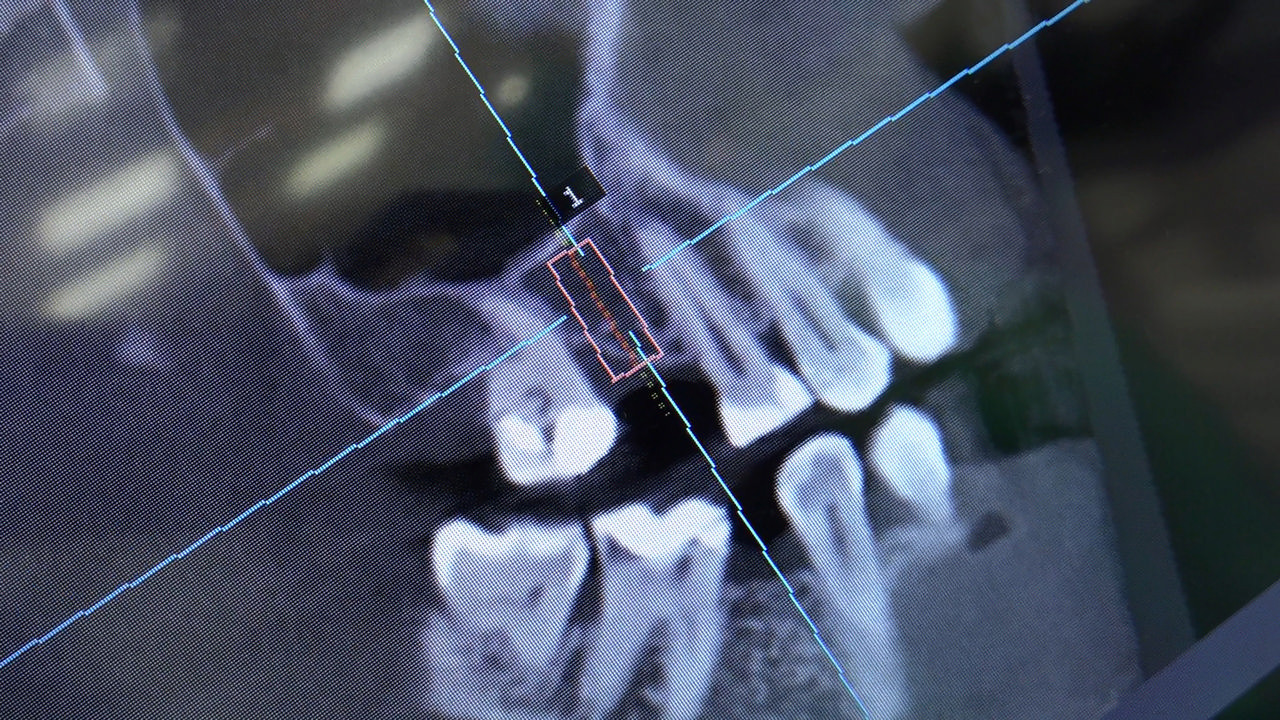

7 Sesja X Sezonu Practiculum Implantologii, w której brali udział kursanci z Grupy A i B, obejmowała implantacje wykonane systemem Axiom, procedury regeneracyjne tkanki kostnej i zabieg sinus lift oraz procedury implantoptotetyczne. Ten zakres szkolenia poprowadziła dr Małgorzata Piotrowska. Protetyka na implantach, to finalny etap leczenia implantologicznego decydujący o uzyskaniu harmonijnego łuku zębowego, okluzji oraz szczelności połączeń, a więc zadowoleniu Pacjenta i powodzeniu całego procesu leczenia.

Jego sednem jest wybór optymalnego rozwiązania rekonstrukcji protetycznej uwzględniający bardzo wiele czynników o charakterze mechanicznym, funkcjonalnym i estetycznym, związanych ze stanem tkanki kostnej, jamy ustnej i uzębienia. Odbywa się już na etapie tomografii komputerowej i jest ściśle powiązany z częścią chirurgiczną, ponieważ prawidłowe zaplanowanie pracy i usytuowania implantów wspomagane plastyką tkanek miękkich, to dla procedur protetycznych baza wyjściowa. Zasady te są jak najbardziej oczywiste, zarówno przy samodzielnym wykonywaniu leczenia implantologicznego, jak i przy podziale zadań dla chirurga i protetyka, czyli pracy w duecie.